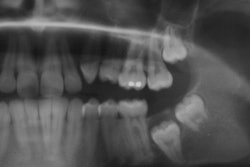

In addition, a link between third molars and periodontal disease is also being studied. Adult African Americans, Hispanics, and those with socioeconomic disadvantages are more likely to have retained their wisdom teeth, making them more at risk for periodontal disease, according to a recent study.